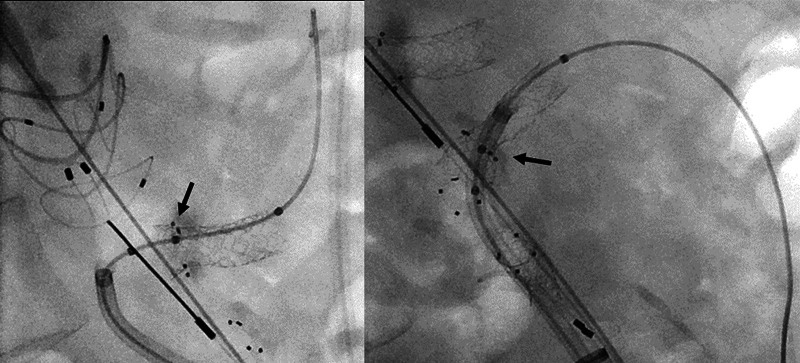

Case description: An 82-year-old male was diagnosed with polyaneurysmal disease. He was treated by femoral, popliteal, and profundal interposition grafts as well as fenestrated endovascular repair (FEVAR) using an Anaconda (Terumo Aortic, Inchinnan, Scotland) endoprosthesis combined with BeGraft peripheral and BeFlared (BF) bridging stent grafts (Bentley InnoMed, Hechingen, Germany).

Conclusion: Polyaneurysmal disease in an aged patient can be treated successfully by thorough case planning, staging of procedures, and combining different vascular surgical techniques. It demonstrates the smooth implantation of the BeFlared in an Anaconda FEVAR.